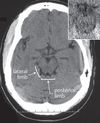

1 = normal CT 2 = Diffuse injury; MLS\<5 mm visible basal cisterns 3 = Diffuse injury; MLS \<5mm compression of the basal cisterns 4 = Diffuse injury; MLS\>5 mm with no mass lesion \>25 cm^3 5 = Evacuated mass lesion 6 = Non evacuated mass lesion (\>25 cm^3)

Decision tree of Marshall classification?